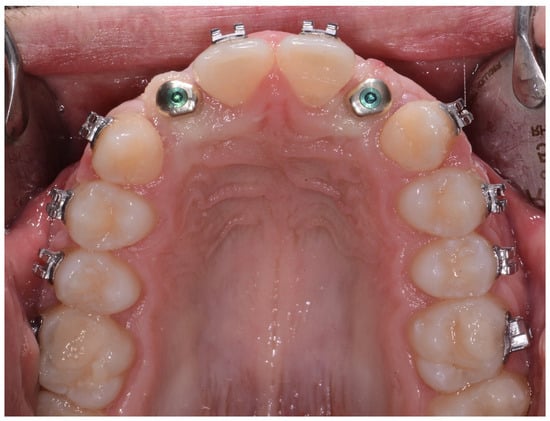

2. Materials and Methods

- 4–10 months: periodontal and orthodontic preparation (if necessary) and implant surgery;